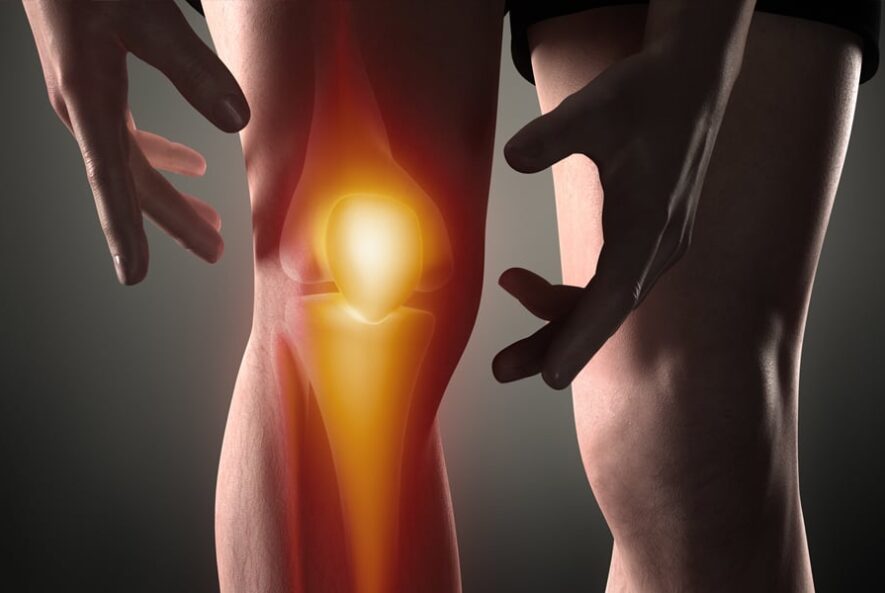

درد مفاصل یکی از شایعترین شکایتها در سنین مختلف است. بسیاری آن را به افزایش سن، فعالیت زیاد یا تغییرات آبوهوا نسبت میدهند. در برخی موارد این دردها گذرا و بیخطر هستند، اما گاهی میتوانند نشانه یک التهاب مزمن، بیماری خود-ایمنی، اختلال متابولیک یا حتی عفونت باشند.تفاوت بین یک درد…